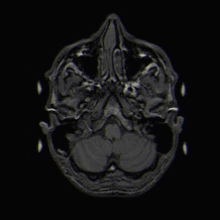

Magnetresonanztomographie

Wird nun das Magnetfeld ausgeschaltet, kehren die Kerne in ihre Ausgangsstellung zurück und geben dabei diese Energie in Form elektromagnetischer Wellen wieder ab. Diese Signale werden von hochempfindlichen Empfängern aus verschiedenen Richtungen registriert und per Computer in Schnittbilder (Tomogramme) umgesetzt.

Da die verschiedenen Gewebearten im Körper unterschiedliche Mengen an Wasser enthalten (z. B. Fettgewebe viel, Knochen wenig), geben sie mehr oder weniger Signale ab und stellen sich damit unterschiedlich, nämlich heller oder dunkler dar.